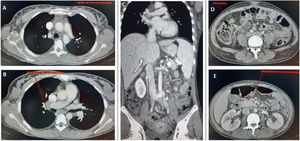

Ganglios linfáticos con linfoadenitis necrosante: necrosis isquémica con vasculitis necrosante (A), vasos periganglionares con trombo rojo (B), hiperplasia folicular con reacción inmunoblástica (C), plasmocitosis e histiocitosis sinusal (D). Presencia de ocasionales microgranulomas (E) (flecha). Inmunohistoquímica positiva para SARS-CoV-2 (F).

La biopsia fue informada como linfadenitis necrosante e hiperplasia linfoide reactiva con histiocitosis sinusoidal extensa, sin que se observaran fenómenos de hemofagocitosis (fig. 1). La PCR para SARS-CoV-2 en ganglio (GeneXpert®, Cepheid) fue positiva. Se inició dexametasona (20mg/día), con mejoría clínica; se retiró la noradrenalina y fue enviada a planta. Allí persistieron los vómitos y citopenias y requirió la transfusión de 2 concentrados de hematíes por anemia. Una biopsia de médula ósea (Appendix B) mostró hipocelularidad moderada, con patrón en mosaico. El ecocardiograma mostró derrame pericárdico leve y función sistólica y coronarias normales. Por último, se diagnosticó de SIM-A, puesto que cumplía los criterios de caso definitivo3. Se añadió inmunoglobulina intravenosa (IGIV) (2g/kg), con mejoría clínica y analítica. Fue dada de alta con corticoides en descenso, ácido acetilsalicílico (100mg/día) y enoxaparina profiláctica. Seis semanas después estaba asintomática y el ecocardiograma era normal, por lo que se retiró el ácido acetilsalicílico.